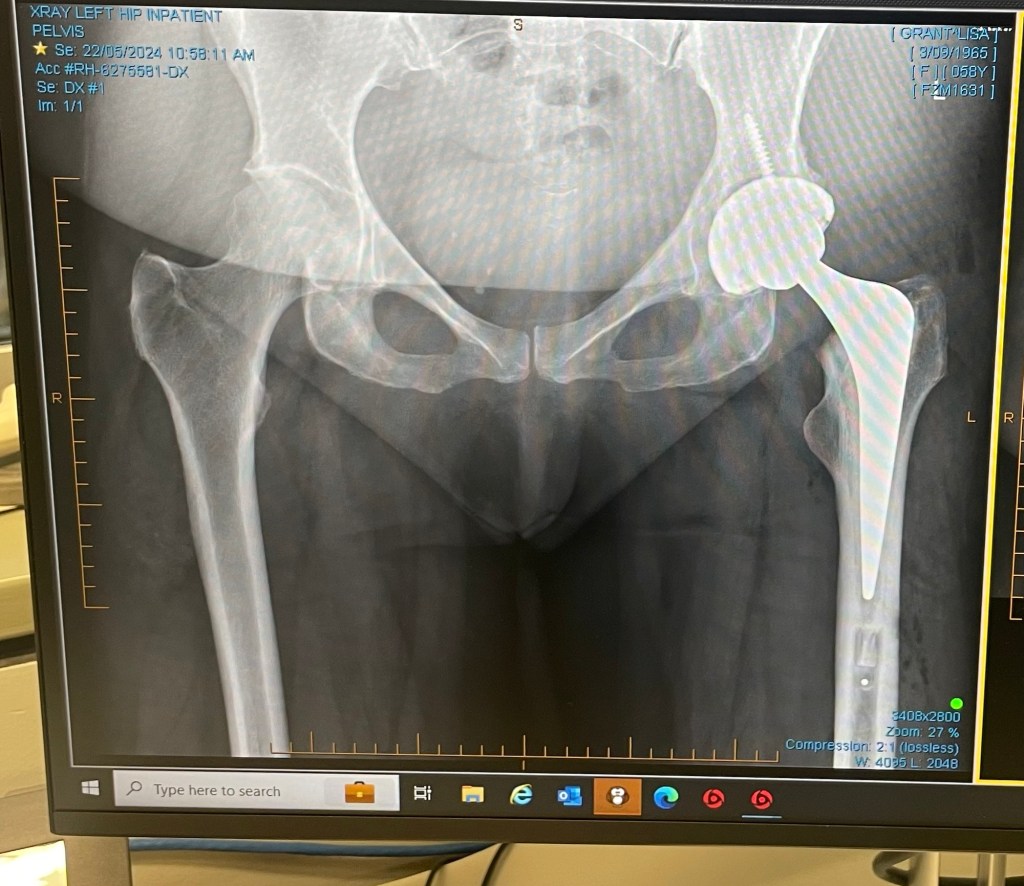

I am still using 1 crutch as I limp without it. Met with the surgeon today he said everyone’s different when I said I wasn’t expecting to still need a crutch. He also said with the method he uses some people end up with a limp for up to a year. π. He also pointed out that my new hip has made my leg longer.